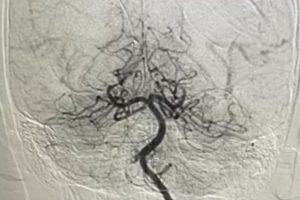

Bệnh viện Nhi Đồng Thành Phố vừa điều trị thành công một trường hợp nhồi máu não cấp hiếm gặp ở trẻ em, giúp bé trai 10 tuổi tránh được nguy cơ liệt nửa người...